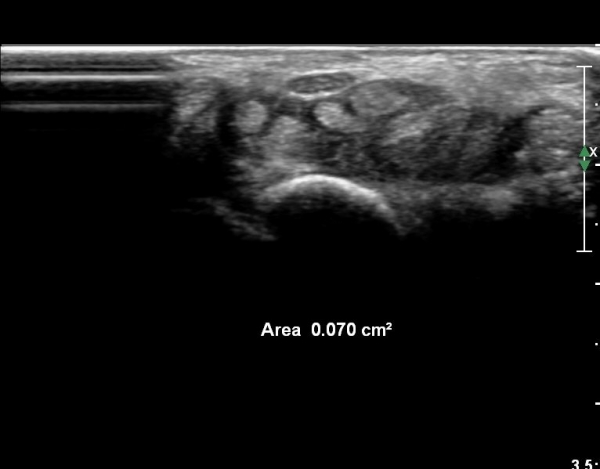

¾Æ·§ÆÈ ¸»´ÜºÎ Ⱦ´Ü¸é°Ë»ç¿¡¼­ ¼Õ°¡¶ô ±¼°î ÈûÁÙÀÇ ºñÈÄ¿Í ÈûÁÙ ½ÉºÎ¿¡ ¼ö¾×Àú·ù°¡ °üÂûµÈ´Ù(»çÁø 1).